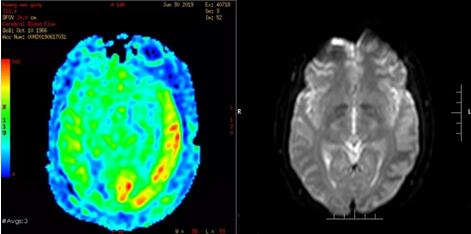

我院头颅MR平扫+增强+DWI检查显示:左侧颞顶叶脑灰质分界增强,局部软脑膜异常线样强化。MR灌注成像:左侧颞枕顶叶弧片状、迂曲线样高灌注影。期间林先生病情突发变化,出现癫痫样发作,随后神志不清,血氧下降至80%-82%,测双瞳孔直径约5mm,对光反射消失,经抢救后,送入我院ICU,生命体征维持平稳。